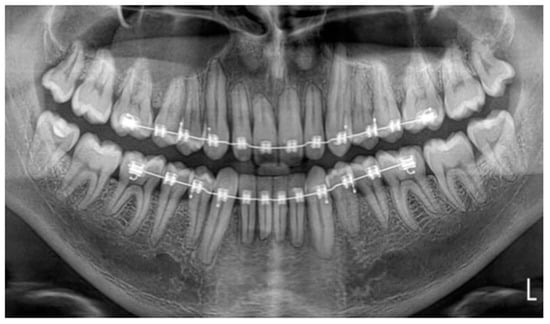

• Therapeutic intervention

Figure 4. Panoramic radiograph during orthodontic treatment for monitoring root resorption.